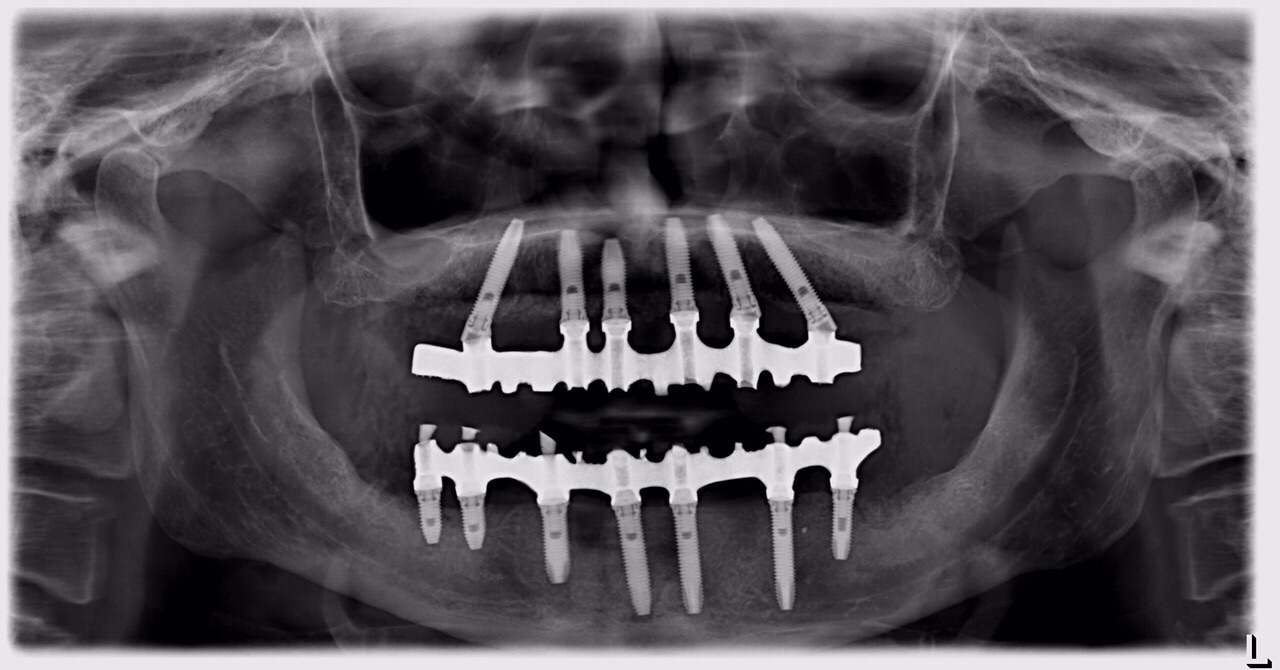

Dott.ssa ERIKA BARBALONGA PIEZOSURGERY in oralchirurgie und direkten IMPLANTOLOGIE Mit der Anwendungstechnik Piezosurgery fuehrt man Eingriffe in Oralchirurgie alls (Aufbau der Kiefernhole, Innenknochen Zystektomie, Wurzelspitzenresktion, komplizierte Extraktionen, Implantatrvorbereitung...) um Traumas zu verhindern und mit Genmanipulazion des Knochens fuer eine rapide Heilung. Ausserdem ist die Verwendung sehr innovativ und effizient fur die Implantatechnik und Knocheregeneration, die uns erlauben Rehabilitazion fur Prothetikpazienten und Steigerung der Stabilitaet der mobilen Prothetik. Mit der direkten Belastung, fixe Zaehne innerhalb in 24 h! Mit geringer invasiven Behandlung und ohne Stress, dank der chirurgischen Piezosurgery - Technik und der Sedierung (Beruhigungsmittel/Narkose) Führen Oralchirurgie mit minimal-invasiven Techniken : - Komplexe Zahnextraktionen ( verlagerte Zähne , überzählige Zähne dysodontiasis ) - Entfernung von Zysten , - Endodontische Chirurgie ( Wurzelspitzenresektion ) - Parodontalchirurgie (Zahnfleisch-Aufklappung , Knoch- und Schleimhauttransplantate ) . - Sinuslift FRUEHERKENNUNG VON MUNDKREBS Unser Engagment in der Foerderung der Kultur der oralen Gesundheit und Praevention im allegemeinen weiterhin hochaktuell, speziell die onkologische Praevention stellt eine der Saeulen unseres Geschaefts. Die fruehzeitige Erkennung von Veraenderungen der Mundschleimhaut erhoehen erheblich die Ueberlebenschancen im Falle von Krebs der Mundhoehle. Fruherkennung bedeutet Gewebeveraenderungen zu entdecken, bevor sie mit blassen Augen sichtbar werden. Die Loesung kommt von Gewebe - Fuoreszenz, die sie tief orale Schleimhautver - aenderungen sehen kann. Mit der speziellen Technologie koennen eine vorbeugende Diagnose untersuchen Bauteilqualitaet orale Schleimhaeute und verwalten werden. BEWUSSTE SEDIERUNG Eine effektive und effiziente Behandlung basiert in der Lage auf, in einer "ruhigen" - Situazion zu behandeln, und dies gilt fuer den Erwachsenen und den kleinen Pazienten. Angst haben, die eine zahnaerztliche Behandlung unterziehen muessen, kann unnoetige Schwierigkeiten fuer den Anwender und Pazienten erstellen. Bewusste Sedierung, mit Nasalmasken oder Intravenoes durch einen Fachmann in Anaesthesiologie, stellt eine therapeutische Waffe an, auf die sie sich verlassen koennen, um diese Themen, sowie eine Reihe von anderen Hilfsmitteln zur Entsspannung des Pazienten zu beheben.

• IMPLANTOLOGIA E CARICO IMMEDIATO